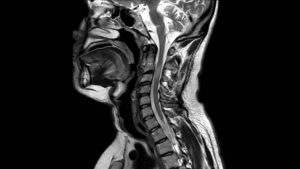

МРТ, или магнитно-резонансная томография – это способ исследования внутренних органов и, что важно при остеохондрозе, тканей с помощью магнитного ядерного резонанса.

Именно такой способ диагностики более предпочтительный на ранних стадиях болезни и для профилактики, чтобы проверить свое здоровье. Он показывает более полную картину при малейших изменениях в тканях, мышцах.

Магнитно-резонансная томография является единственным методом, позволяющим увидеть патологические и структурные изменения в шейных позвонках, а также оценить патофизиологические и физико-химические процессы в шейном отделе позвоночного столба. МРТ шейного отдела показывает в трехмерном изображении нервные стволы и сосудистую сеть позвоночника.

МРТ шеи обладает высоким качеством, поэтому считаются одной из лучших диагностических процедур. Оно не является альтернативной заменой компьютерной томографии, так как у этих методик разное назначение.

Магнитно-резонансная томография головы и спинного мозга позволяет четко проследить состояние мягких тканей, насыщенных водой. Компьютерное сканирование позволяет исследовать костную систему: позвонки, структура костей.